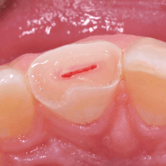

Pulpitis Crónica Hiperplásica

La pulpitis crónica hiperplásica es una inflamación de la pulpa con crecimiento excesivo de tejido pulpar a través de una caries abierta.

Los pacientes notan un tejido rojo que sobresale de la cavidad dental.

El tratamiento incluye la eliminación del tejido afectado y un tratamiento de conducto. Es crucial tratar la caries para evitar infecciones adicionales.